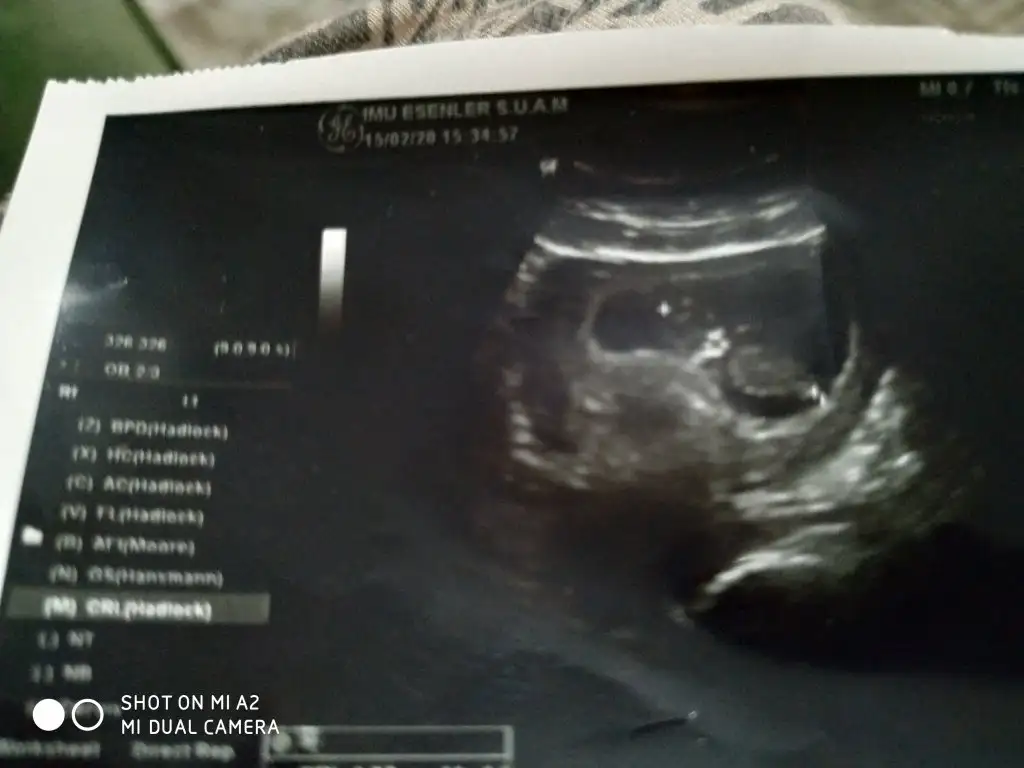

Bu 13 haftalıkEki Görüntüle 2591468

Bu gördüğüm nub ise erkek kaç haftalık usgleryakınlaştırın yeşil çizginin üstünde nubu var karşıya bakıyor çözemedim usgleri